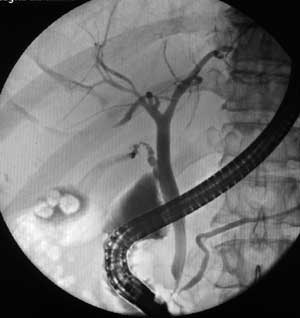

Рентгеноскопия + эндоскопия = ЭРХПГ.

Рис. 1. Нормальное “дерево” желчевыводящих протоков и холецистолитиаз. Хорошо видны законтрастированные внутри- и внепеченочные желчные протоки, панкреатический проток, камни в желчном пузыре.